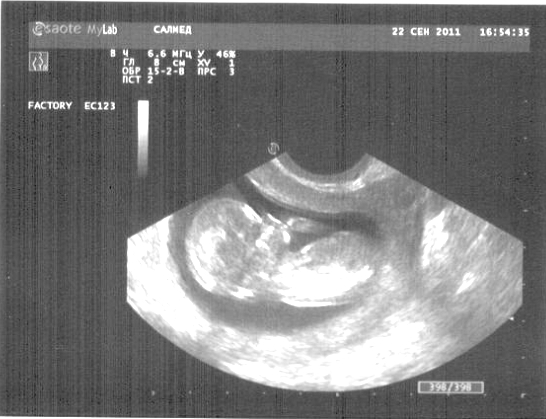

Девочки, хочу представить мою лялечку ))))))))

Вложения:

малыш2.jpg

малыш2.jpg [ 133.54 КБ | Просмотров: 1432 ]

Lunamaster, хорошенький такой)))))Поздравляю!!!! :chmok: Пальчик что ли сосет....

а пол не сказали?

Пасибки, девочки!!!! Вот и смотрю..большая что-то..хотя мама сказала, вся в меня...у меня мозг большой)))))) и родилась я бутузом! Савушкина больше склоняется к девочке :-) и я тоже если честно! Пальчик сосет моя козява)))))